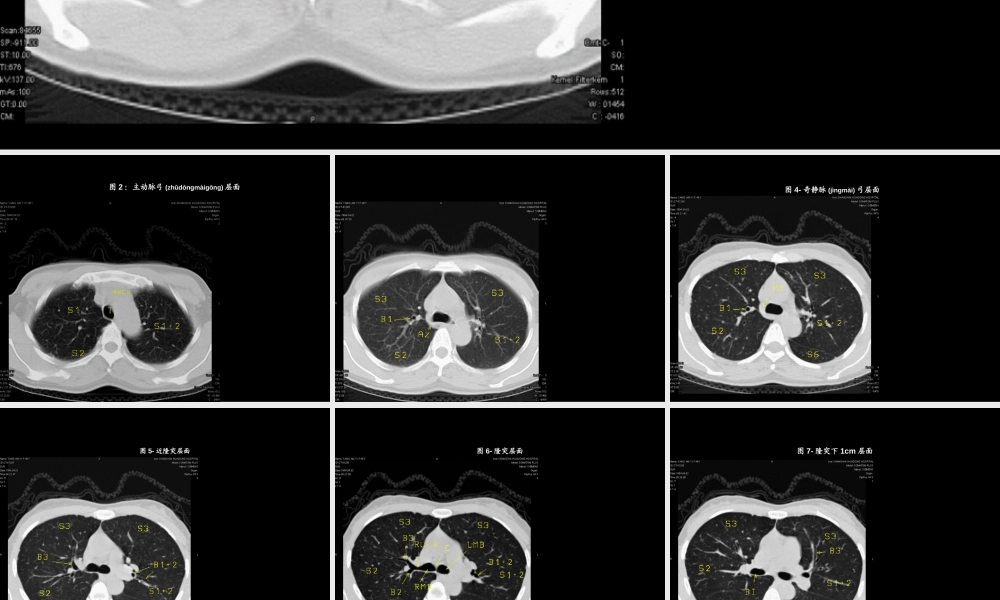

图1-16:正常胸部断层(duàncéng),图1-胸锁关节(guānjié)层面第一页,共八十一页。图2:主动脉弓(zhǔdòngmàigōng)层面ARCH:主动脉弓(zhǔdòngmàigōng)第二页,共八十一页。Az:奇静脉(jìngmài)弓B1:上叶尖段支气管S3:上叶前段图3-主肺动脉窗层面第三页,共八十一页。图4-奇静脉(jìngmài)弓层面S6:下叶背段第四页,共八十一页。图5-近隆突层面B1+2:左上叶尖后段支气管B3:上叶前段支气管第五页,共八十一页。图6-隆突层面第六页,共八十一页。图7-隆突下1cm层面Bi:中间(zhōngjiān)支气管第七页,共八十一页。图8-隆突下1cm层面LUMB:左上叶支气管第八页,共八十一页。图9-隆突下2cm层面V3:上叶前段静脉(jìngmài)的段间支第九页,共八十一页。图10-隆突下2cm层面S4:右中叶(zhōngyè)外段/左舌上段第十页,共八十一页。图11-隆突下3cm层面B4:右中叶(zhōngyè)外侧段/左舌上段支气管第十一页,共八十一页。图12-隆突下3cm层面B6段第十二页,共八十一页。图13-隆突下3cm层面第十三页,共八十一页。图14-近心底(xīndǐ)层面5右侧段/段第十四页,共八十一页。图15-近心底(xīndǐ)层面B7+8:下叶前内段支气管第十五页,共八十一页。图16-近心底(xīndǐ)层面B段第十六页,共八十一页。图17-锁骨(suǒgǔ)上和斜角肌组淋巴结应扫描从锁上膈上锁上和斜第十七页,共八十一页。图18-1R/L组淋巴结肺臂静脉横入右臂静第十八页,共八十一页。图19-1R/L组淋巴结第十九页,共八十一页。图20-1R/L、3A/P组淋巴结肺动脉上缘层前组组第二十页,共八十一页。图21-2R/L组淋巴结侧淋右/第二十一页,共八十一页。图22-4R、6组淋巴结位于主动脉弓(zhǔdòngmàigōng)上缘以下主动脉、主动脉弓前方及两侧的淋巴结-为升主动脉旁组(6组)第二十二页,共八十一页。图23-4R/L、6组淋巴结还可静脉界将右侧4组第二十三页,共八十一页。图24-4R/L、5、6组淋巴结淋-动脉或第二十四页,共八十一页。图25-7组淋巴结组第二十五页,共八十一页。图26-7、10R组淋巴结淋-右/肺组第二十六页,共八十一页。图27-8、10R/L组淋巴结右/8R/L组第二十七页,共八十一页。图28-9、11R组淋巴结肺静脉周淋第二十八页,共八十一页。图29-12、13、14R/L组淋巴结邻近各肺段淋第二十九页,共八十一页。图30-肺间质病变(bìngbiàn)常规(chángguī)或标准CT扫描、重建第三十页,共八十一页。图31-肺间质病变(bìngbiàn)建第三十一页,共八十一页。图32-肺间质病变(bìngb...